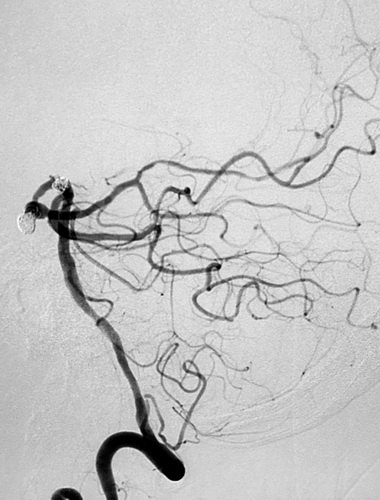

全脑血管造影提示:左侧颈内动脉主干血管明显狭窄,大脑中动脉及前动脉基本闭塞,左侧供血差,颈外动脉有少量代偿,左侧椎动脉造影示右侧大脑后动脉P2段夹层、基底动脉顶端,分别大小为6 mmX5mmX4mm瘤颈约5mm;4 mmX4mmX3mm瘤颈约3mm。

ICA造影

首先栓晒右侧大脑后动脉瘤

右侧大脑后动脉瘤术后侧像